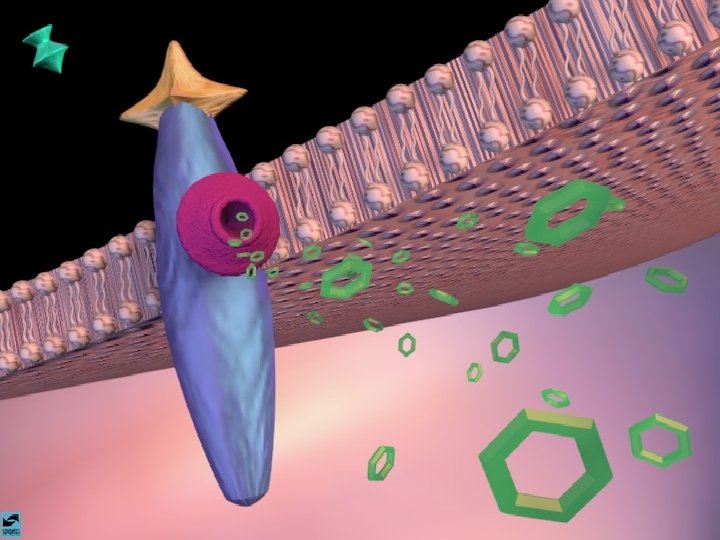

A AÇÃO DAS DROGAS NO SISTEMA NERVOSO CENTRAL A SINAPSE

A AÇÃO DAS DROGAS NO SISTEMA NERVOSO CENTRAL OS NEUROTRANSMISSORES - NORADRENALINA - SEROTONINA - DOPAMINA - GABA - ACETILCOLINA

ANFETAMINAS E COCAÍNA EFEITOS CEREBRAIS: ATIVA OS SISTEMAS DOPAMINÉRGOS MESOLÍMBICOS E MESOCORTICAIS, INIBINDO A RECAPTAÇÃO DE DOPAMINA NOS TERMINAIS SINÁPTICOS E PROMOVENDO SUA LIBERAÇÃO NAS SINAPSES.